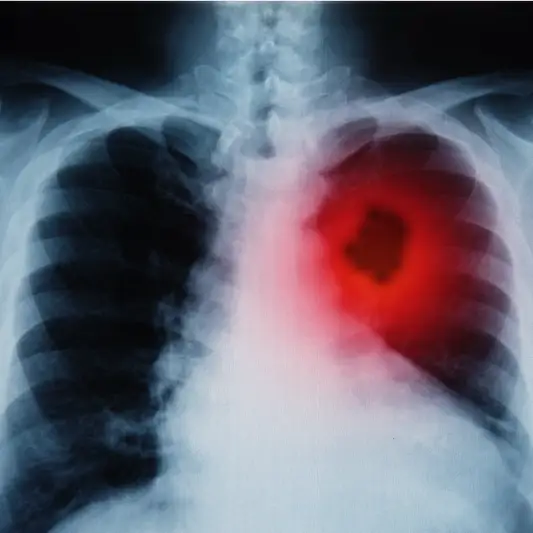

폐암 1기 진단을 위해서는 정기적인 검진이 중요합니다. 폐암 검진에는 흉부 X-선, CT 스캔, PET 스캔 등이 사용될 수 있습니다. 이러한 검사를 통해 의사는 폐암의 존재 여부와 정확한 위치를 확인할 수 있습니다. 또한 폐암의 크기, 종류, 세포의 특성 등을 파악하여 적절한 치료 방법을 결정할 수 있습니다.

폐암 1기는 폐조직 내에서 악성 종양이 형성되었음을 의미합니다. 이 단계에서는 종양이 아직 주변 조직으로 번지지 않고 지역적으로 제한되어 있습니다. 따라서 초기 폐암 치료는 주로 수술로 이루어집니다.

폐암 1기 진단과 초기 치료 방법도 매우 중요합니다. 폐암이 조기에 발견되면 암세포가 아직 주변 조직으로 확산되지 않았을 확률이 큽니다. 이 경우 수술이나 방사선 치료 등의 치료 방법을 통해 암세포를 제거하고 치료할 수 있습니다. 하지만 발견이 늦어지면 치료가 어려워지고 생존율이 현저히 낮아질 수 있습니다.